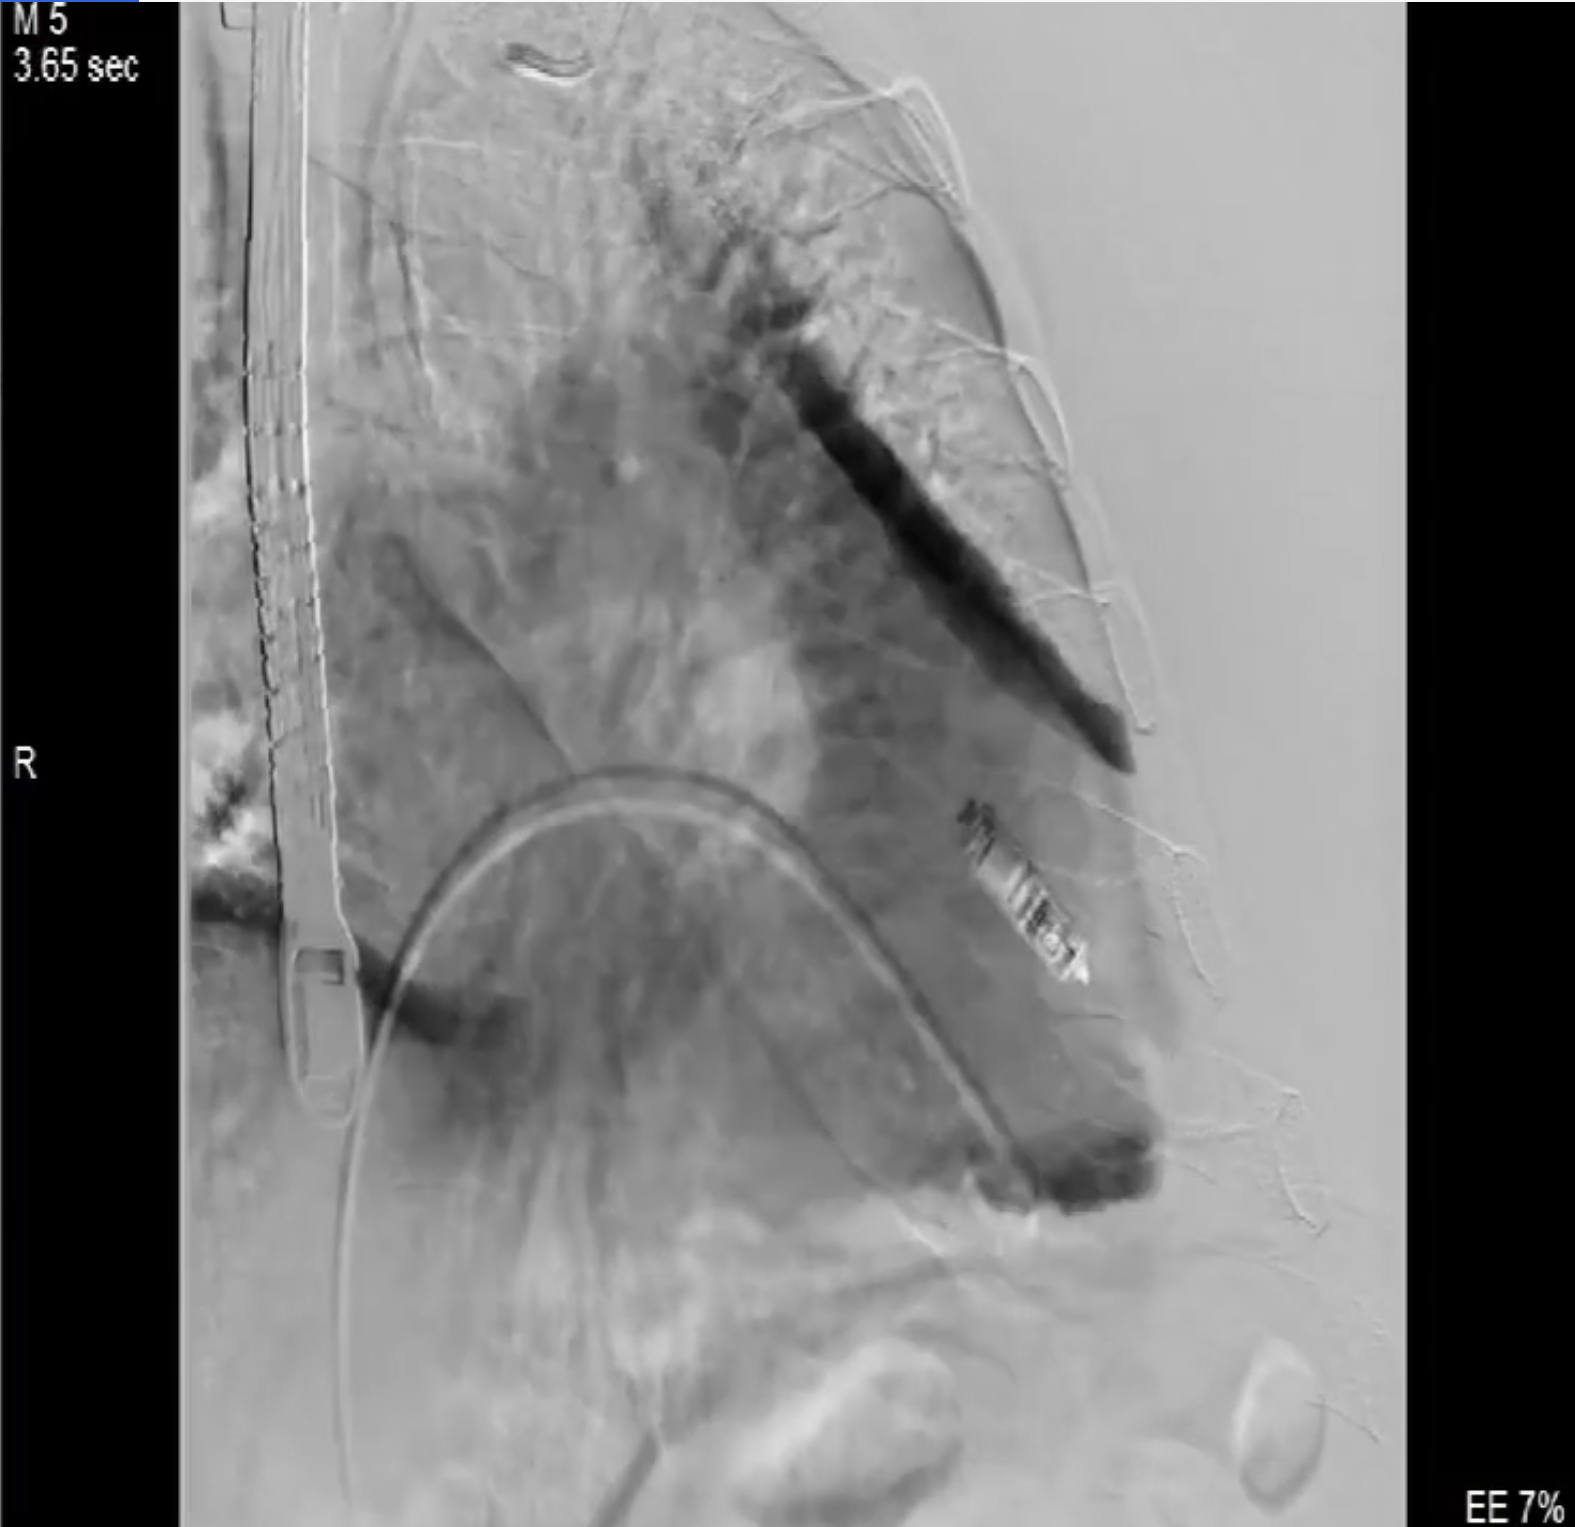

術中影像

術前DSA造影可見三尖瓣大量返流呈瀑布樣,右室偏間隔側可見無導線起搏器一枚。

本次直播手術中,手術團隊在超聲與DSA等多維影像手段的支持下,精準嫻熟的完成LuX-Valve Plus瓣膜的植入,器械操作時間僅為30分鐘,瓣膜植入后術中即刻三尖瓣返流消失,多普勒超聲下無明顯瓣周漏或中心性返流,肺動脈壓正常,平均跨瓣壓差僅為1mmHg,人工瓣膜運動正常,術后1小時內該患者即安返病房。